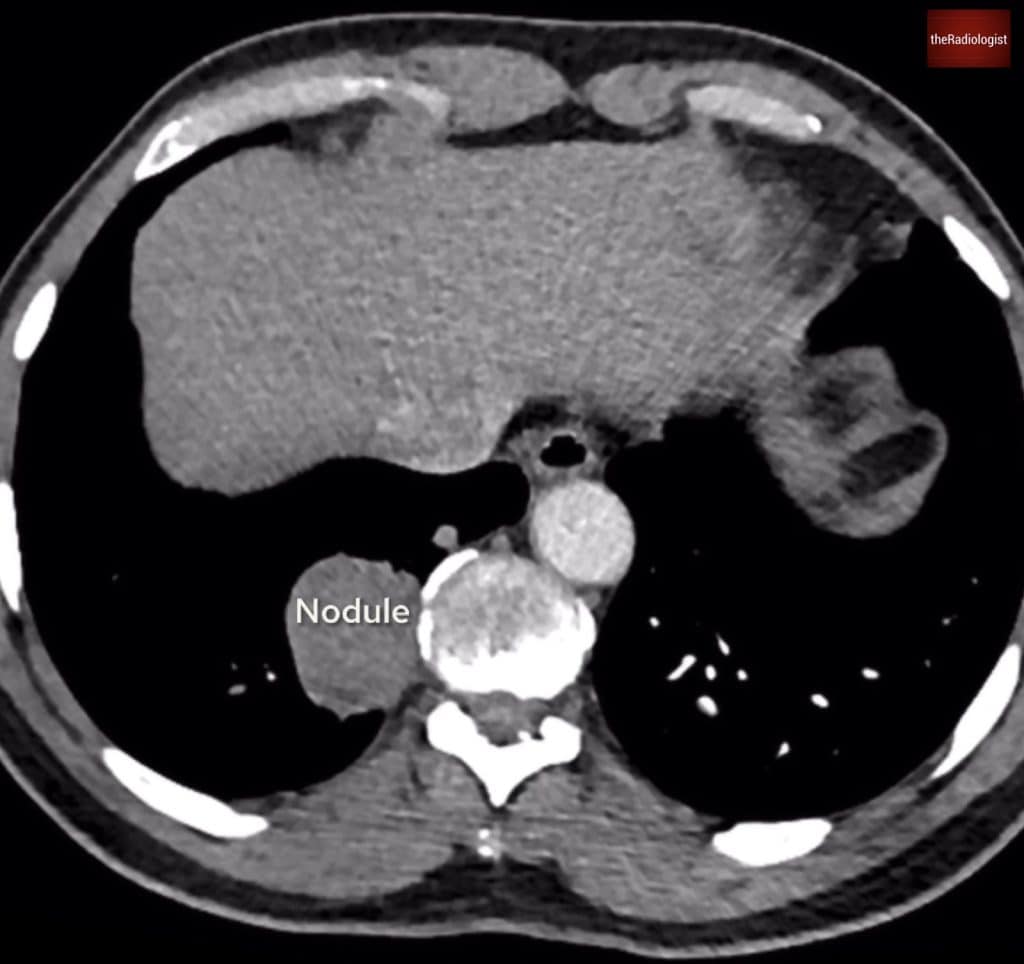

2. Searching for underlying malignancy

Finally, it’s important not to overlook the bigger picture. PE is frequently provoked, and in many cases, malignancy is the underlying driver. A thorough review of the lung parenchyma is essential, particularly for masses or nodules that might suggest a primary lung tumour or metastatic disease.

Equally, reviewing the upper abdominal cuts can sometimes reveal previously undiagnosed malignancies, including pancreatic, adrenal, or hepatic lesions.

Underlying malignancy

Have a look at lung windows and there are multiple pulmonary nodules, the largest located in the right lower lobe. The upper abdominal cuts were unremarkable, but the presence of multiple nodules raise concern for metastatic disease.

There are multiple lung nodules with the largest within the right lower lobe.